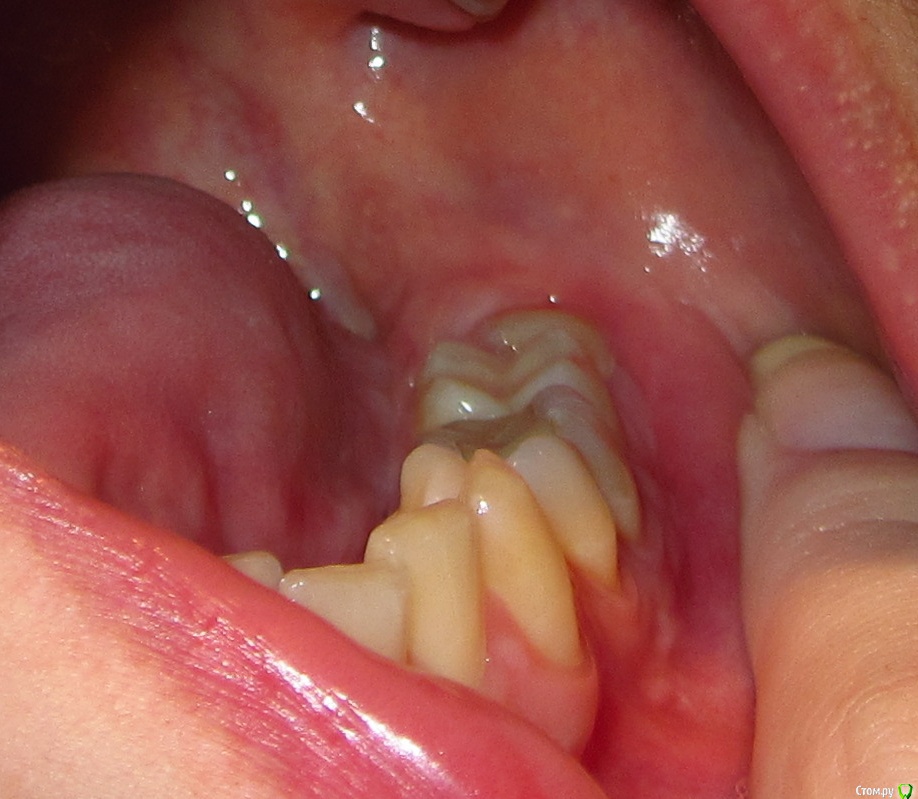

aqua1 Опубликовано 8 февраля, 2015 Автор Поделиться Опубликовано 8 февраля, 2015 (изменено) Разъяснения по снимкам:1) весна 2008 года - начало2) 2009 год3) весна 2012 года - сразу после обострения и появления отвердевшей десны4) свежий снимок 2015 года5) так выглядит зуб мудрости4) зубы и десна в обычном состоянии7) и 8) - изображения отвердевшей дуги на десне вдоль 6, 7 и 8 зубов (т.е. та область, что между зубами и пальцем) Изменено 8 февраля, 2015 пользователем aqua1 Ссылка на комментарий